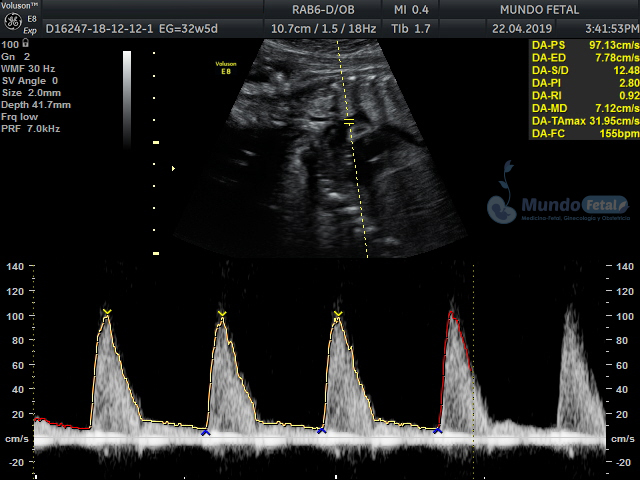

Se recomienda de 32-34 semanas, realizando valoración de crecimiento armónico (4 medidas específicas), valoración anatómica, líquido amniótico, flujos sanguíneos fetales y placentarios perfilando el bienestar fetal hacia el final de embarazo.